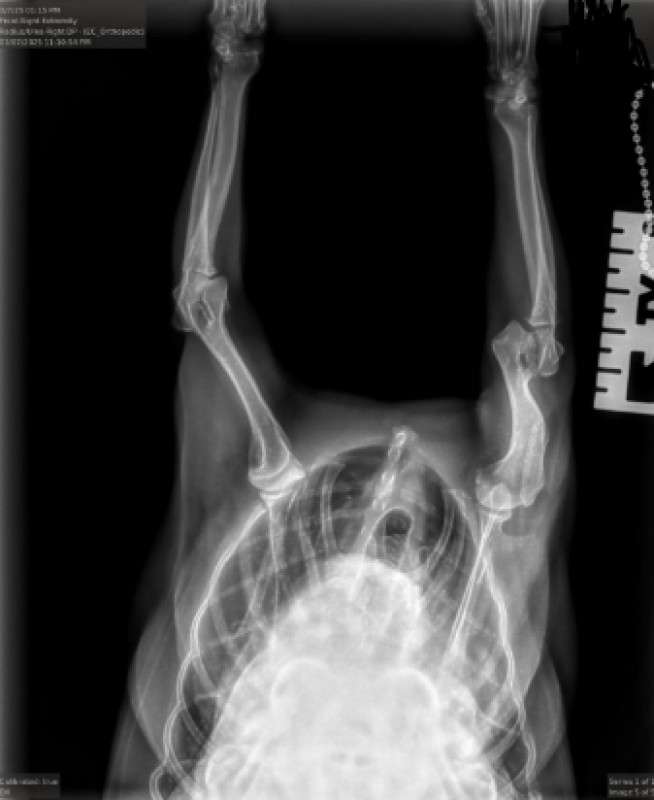

"Becca has an articular fracture of her right elbow that is now chronic. On repeat x-rays today,

the fracture has further displaced and this is not a fracture that will heal on it's own. Open surgical reduction to reduce and stabilize the

fracture or amputation are the best treatment options. If surgical intervention is not possible, I would remove the bandage/splint in 2-3

weeks as we will have sufficient scar tissue formed that the splint/bandage will no longer help her and we will eliminate the risk of

bandage complications.

Surgery involves an open approach to the elbow, reduction of the fracture fragments and stabilization with a trans-condylar bone screw

and anti-rotational pin. Given her age, I have also recommended a minimum of one shockwave treatment to stimulate bone healing.